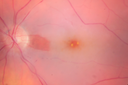

Choroidal Nevus in Macula 822 views